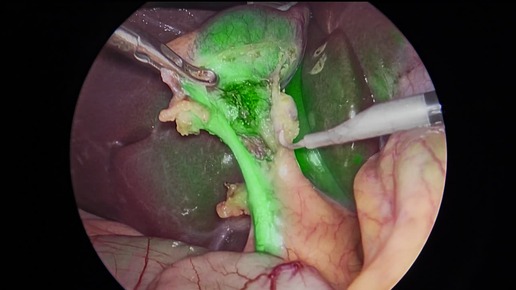

ICG - навигация в действии: новый уровень безопасности при холецистэктомии.